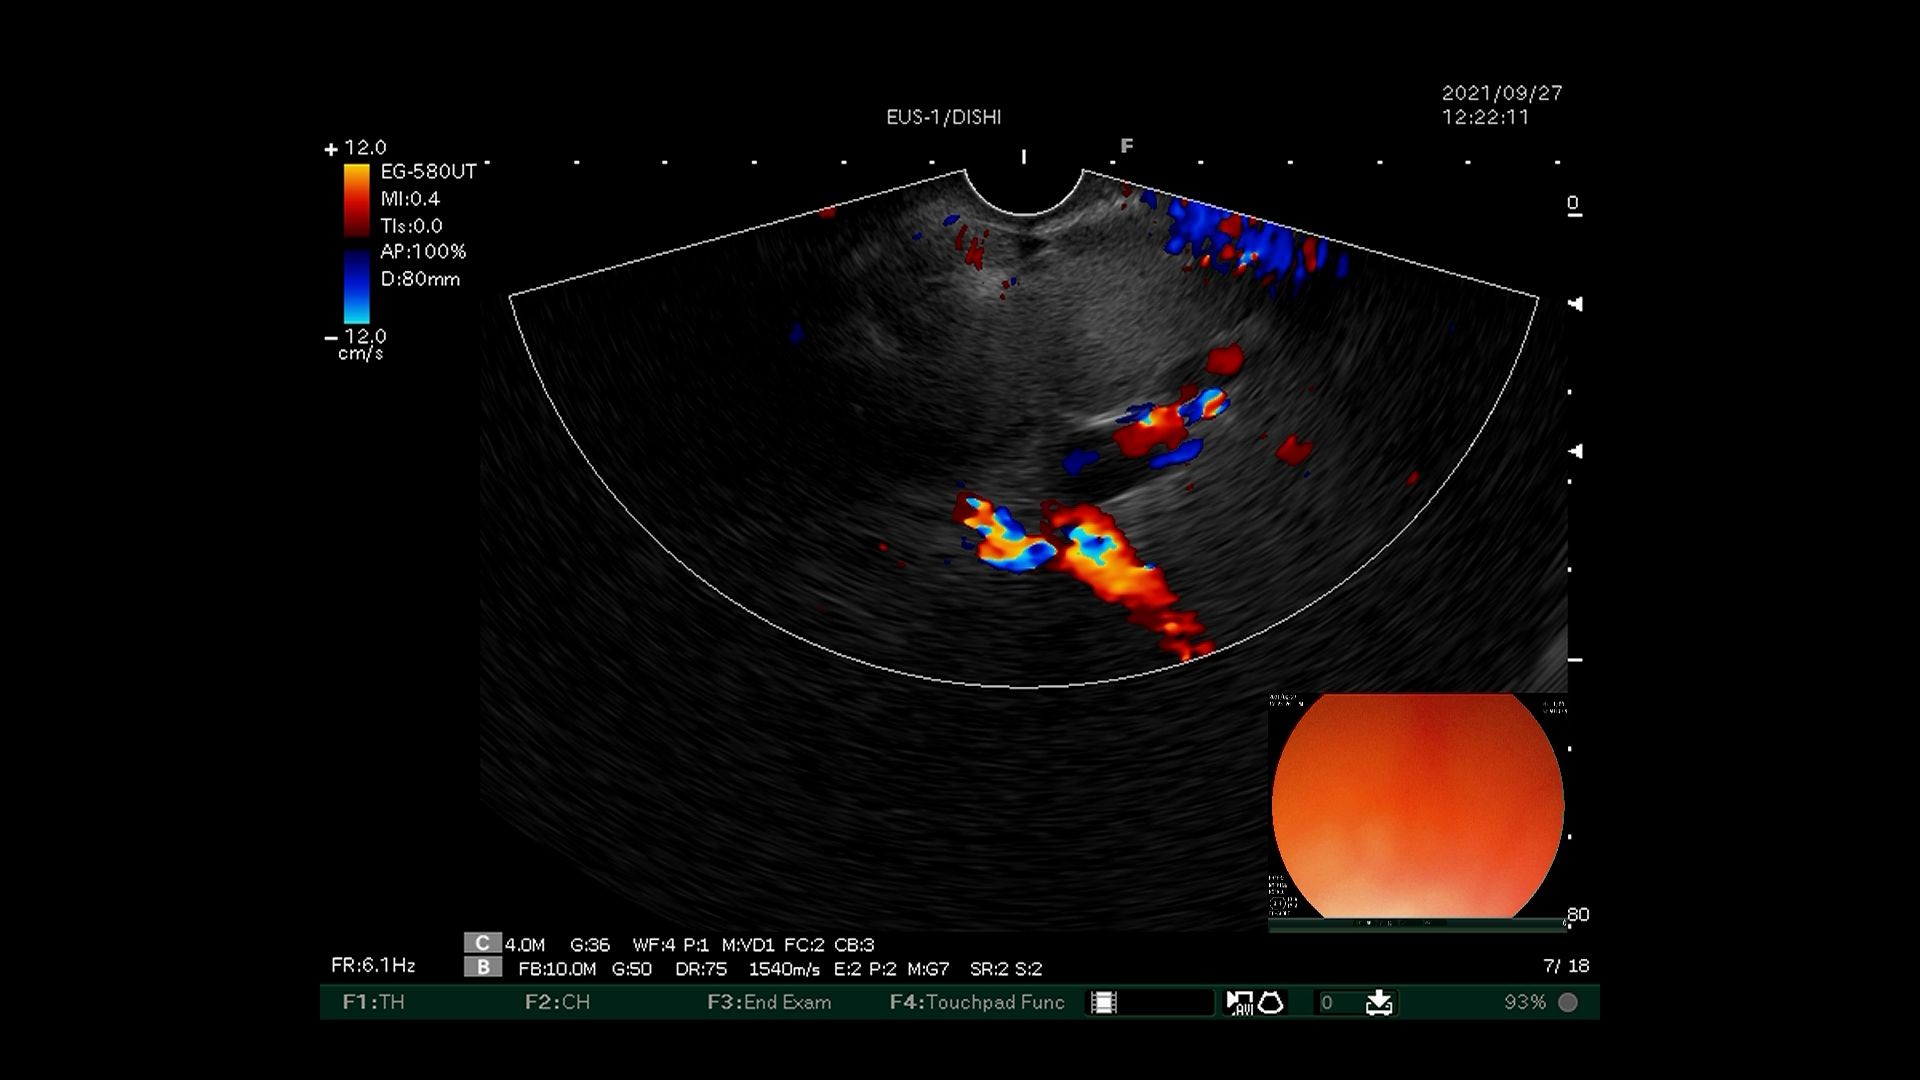

3)超声内镜下多普勒观察内部有丰富血流信号。

6)超声内镜确认曲张静脉血流信号消失。